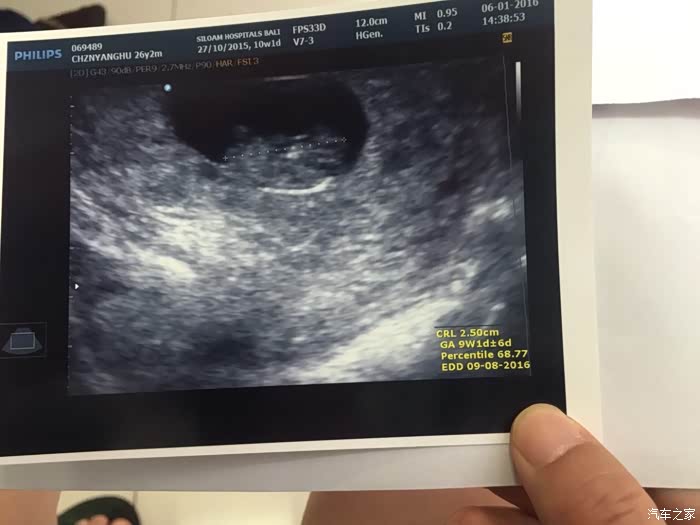

等待排队叫号。在检查之前,护士对我做了详细的调查,了解了我的各项情况之后,带我去看医生。很纳闷,妇产科的医生居然男的居多。

医生将仪器放在我的肚皮上,我和老公的面前有一个巨大的电视,医生告诉我,宝宝很好,很健康。医生还让老公也凑过来,也听听宝宝很急促的心跳

。透过电视,我们可以清晰的看见,宝宝的胳膊和腿在妈妈的肚子里使劲的划来划去,好像自己是一个出色的游泳健将。这相当于我的第一次产检,我们第一次清晰的看见我们的孩子,当着医生的面都要激动的掉眼泪了。这是第一张帮宝宝在巴厘岛拍的照片,我们好好地给他保存起来,等他落地的时候,应该会有好多有趣的故事讲。